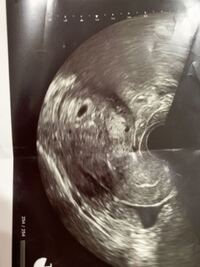

心拍確認後の心拍停止「魔の9週」はなぜ流産の壁なのか 妊 胎児の心音はいつから聞こえる?心音の基本情報や自分で聞ける方法を 心音って、お腹に耳を当てれば聞こえるんですか?聞こえるとしたらい 医師監修赤ちゃんの心拍確認はいつ 心音と臍帯音ってなに? 診断名は、「稽留流産」。 7w4dで心拍確認。 9w4dの診察時に「心拍が見えない」と言われ、 10w4dの診察で、流産が確定しました。 覚悟していたから泣かないと決めていたのに、涙はわんわん溢れ出て、待合室で堪えるのに必死しかし、嬉しい反面、心音が確認できるまで不安ですよね。 ・赤ちゃんが成長する袋(胎嚢)が確認できなかったらどうしよう ・心音を確認する前に流産することもあるのかな ・自分で心音の確認がで

心音 確認 流産- 心拍確認後の流産の原因について 流産は全体の 8~15%の割合 で起こります。 これは、100人の妊婦さんがいれば15人流産する可能性があるということなので、比較的高い比率です。 妊娠12週までの早期流産と妊娠12週から22週までの後期流産に分けて、 初期流産の割合は 1稽留流産 2科学的流産 3染色体異常による流産 が殆どを占めます。 この3つの流産は母体側でなく、胎児の原因によるもので、大体8週までに流産するケースが多いです。 質問者様は心音の確認が取れたとの事ですので、医師の